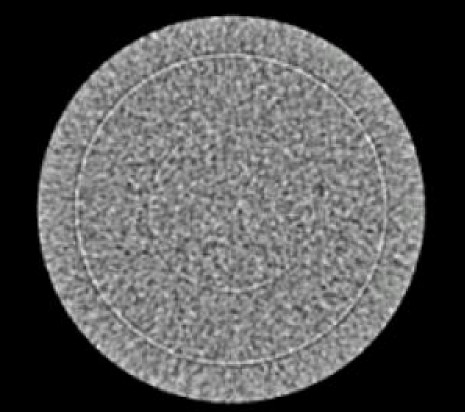

This troubleshooting procedure and associated Service Tool is designed to be used on systems using the interposer design. This includes all MDAS 16-slice and GDAS 16-slice systems. It is intended to be used to troubleshoot rings (Figure 2) and isolate problems between the rings and the DAS or Detector.

Figure 2. Typical Ring Artifact